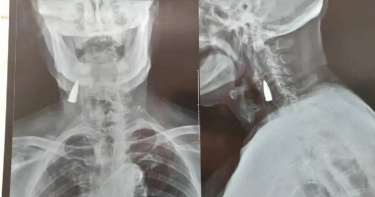

95歲老兵意外摔倒就醫發現「頸部卡子彈」 他憶起:抗日戰役留下

大陸山東臨沂一位95歲抗戰老兵摔倒後,拍X光發現頸部有一顆戰爭時期留下的子彈,據這位長者的女婿王先生稱,岳父參加過抗日戰爭、解放戰爭和抗美援朝戰爭,據回憶,岳父是在抗日戰爭時期受的傷,身體別的地方也有彈片,沒留意到這顆子彈。山東臨沂一位95歲抗戰老兵摔倒後,拍X光發現頸部有一顆戰爭時期留下的子彈。根據《每日星報》和大陸《人民日報》報導,王先生表示,岳父趙合今年95歲,平時身體還不錯,跟岳母同住,生活自理沒問題。10月20日,岳父不慎摔了一跤,事後覺得臀部和脖子疼。隔天,他就帶岳父到當地醫院做檢查,經過拍片發現岳父的頸部離動脈很近的地方,居然有一顆子彈,「當時我就震驚了,家裡其他人知道了也都很震驚」。這名長者回憶,這顆子彈可能是在抗日戰爭時期一場戰役中留下的。這名長者過去因腰疼拍過X光,發現其腰部有彈片遺留,後來又因頭疼就醫,也做過頭部、胸部的相關檢查,「脖子之前一直都沒有不舒服,也沒拍過片,剛好成了檢查盲區」。王先生和家人也是現在才知道岳父頸部還遺留著子彈,「做了檢查發現他骨頭沒問題,主要是摔跤引起臀部和脖子肌肉疼痛」。目前,老人家身體狀況良好,他自己表示不想取出子彈,醫生也尊重老人家的意願。老人發現頸部遺留子彈引發關注後,王先生也向其詢問了這顆子彈的來歷,據其岳父自己回憶,這顆子彈可能是在抗日戰爭時期一場戰役中留下的,當時老人所在的一個排共54人,但那場戰役結束後只剩下了6個人,而且存活下來的人受傷都比較嚴重。老人回憶後稱,「當時子彈是從鼻子左邊打進去的,他口腔內上顎的一塊皮肉脫落,還掉了4顆牙,當時沒找到子彈頭,就自以為從嘴裡出去了,但其實應該是穿透了下顎軟組織後掉在了頸部」。他說當時身上其他部位受傷更嚴重,因此就忽略了頸部的傷。這些年也並沒發現什麼異樣,直到這次拍片才發現子彈。